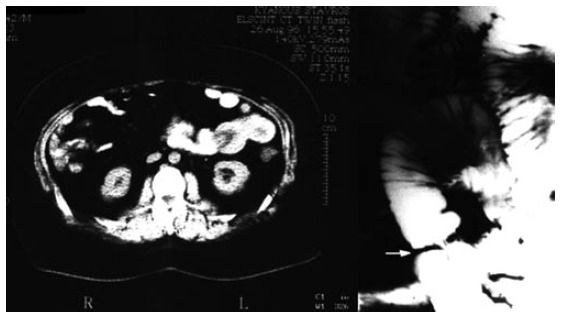

During the second episode, hemoglobin was 8.8 g/dL and the pain had become constant. Repetition of esophagogastroduodenoscopy and colonoscopy revealed no special findings. On the contrary, CT scan showed marked small bowel wall thickening and also detected a leading point with fat density (Figure 1). Small intestinal intussusception caused by a lipoma was considered to be a probable diagnosis. Abdominal conventional radiographs showed dilation of the jejunum and enteroclysis demonstrated an obstructing lesion (Figure 1).